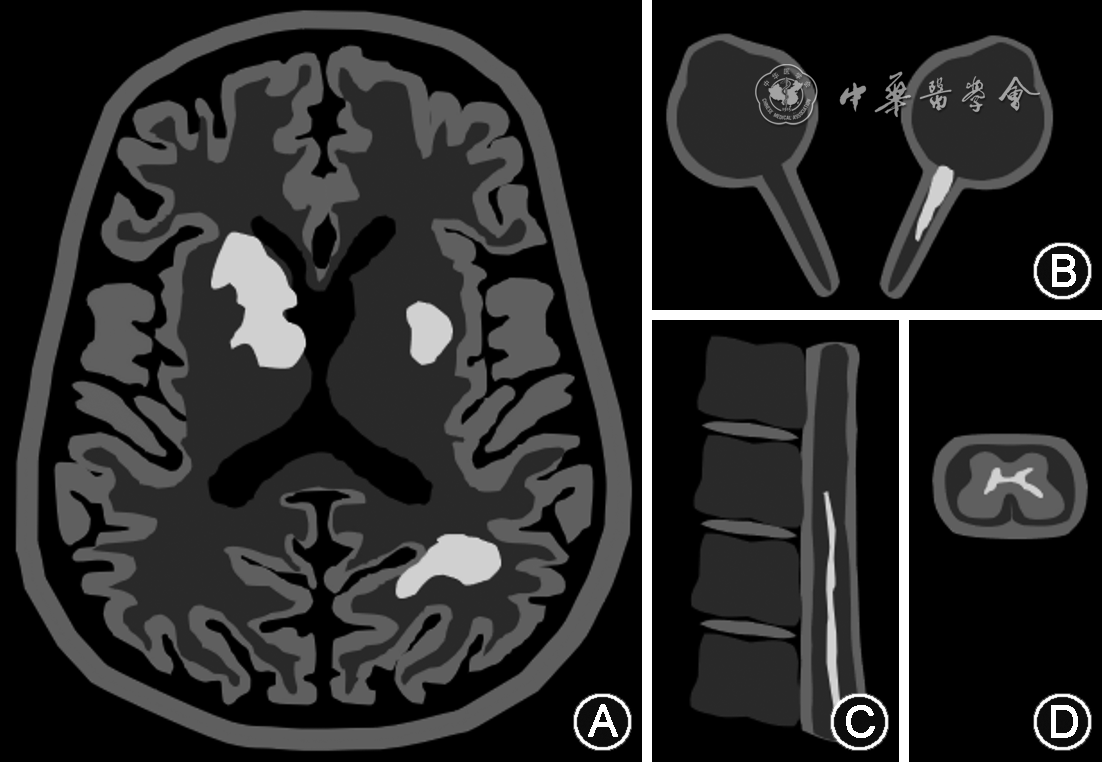

MOGAD患者的MRI增强结果表现出一些特点或能辅助诊断的建立(图1)。

1.头颅MRI:头颅MRI病灶可见于50%的MOGAD患者[12]。ADEM患者常出现较大、模糊、边界不清的不对称双侧病灶[30],可位于皮质、皮质下、深白质及深灰质,以丘脑多见,且可高度强化。同时,在出现脑炎及癫痫的MOGAD患者中也可出现皮质或皮质周围的可逆性病灶,偶尔会有软脑膜的强化以及皮质下白质边界弥散的T2像信号灶,增强不明显,可能伴有皮质下灰质萎缩[31, 32]。除此之外,40%的MOGAD患者可出现脑干病灶,尤其是位于脑桥以及小脑中脚(middle cerebellar peduncle)的病灶[30]。

2.脊髓MRI:MOGAD患者脊髓MRI可表现为类似 NMOSD的长节段T2高信号灶,但其中也有40%为短节段脊髓病灶[30]。MOGAD的特征性病灶位于脊髓圆锥,局限于灰质与神经根(矢状位线样征与横断面H征),不伴T1强化[32]。有时范围较大的病灶可伴有较轻的临床表现[21]。

3.视神经MRI:MOGAD患者的视神经MRI可见位于前侧视神经或视交叉的T2高信号及钆增强灶,病灶较长,大于1/2视交叉前视神经长度,可伴周围强化[32]。